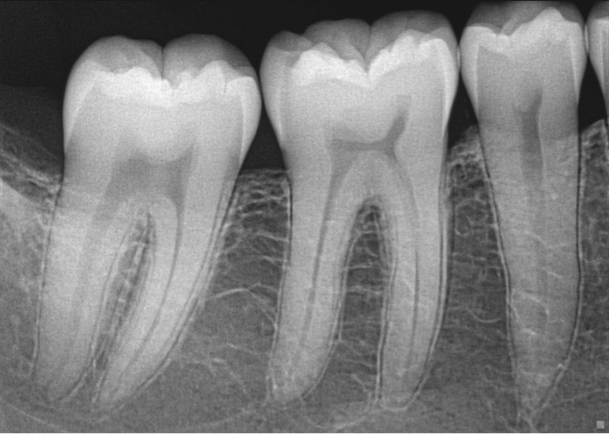

Periapical images show the teeth and supporting bone with great amount of detail. These images are used to identify dental cavities and abnormalities involving the bone adjacent to the teeth.